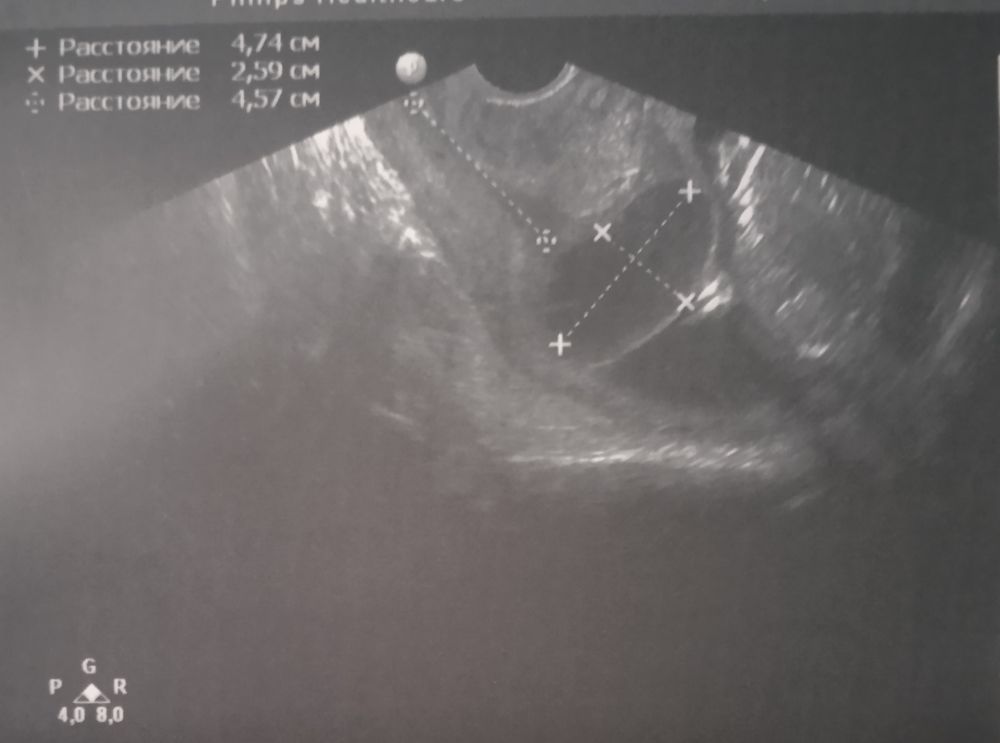

17 недель, мальчик)

17 недель Определение пола по крови.Куда пойти в Москве?